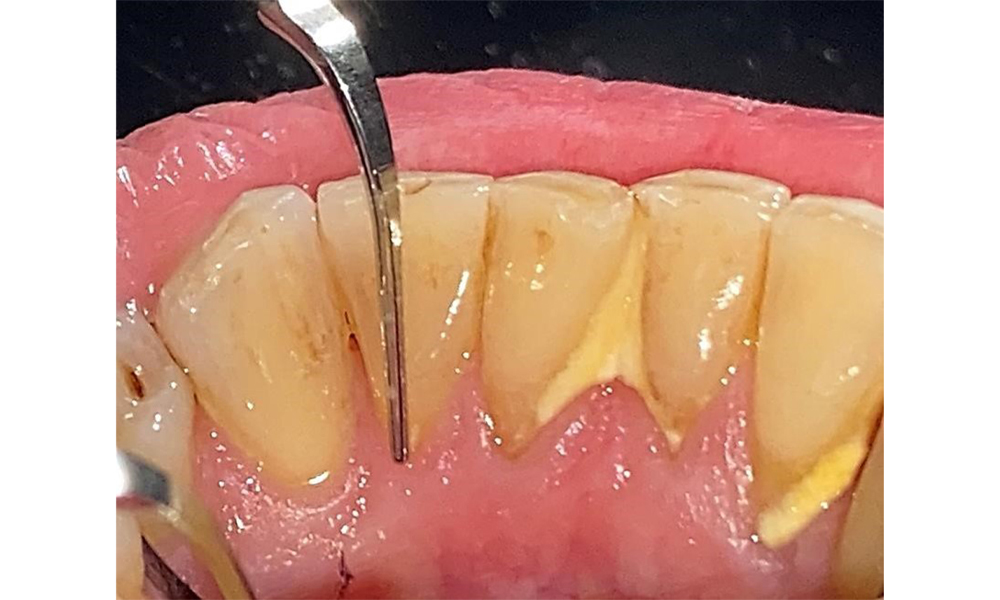

Der Patient hat eine Parodontitis Stadium II, Grad B (5). Die klinischen Sondierungstiefen liegen mit 1-3mm im physiologischen Bereich. Lokalisierte Sondierungstiefen finden sich an 17 und 27 jeweils mesiopalatinal mit 5mm. Es liegen generalisierte Rezessionen von 1-3mm vor mit partiellem Verlust der Interdentalpapillen (Abb. 2, Abb. 3, Abb. 4)

Der Patient ist ein gut eingestellter Diabetiker. Somit ergibt sich aus der Anamnese kein erhöhtes Komplikationsrisiko für die Behandlung. Grundsätzlich ist vor jeder Behandlung der HbA1c-Wert abzufragen. Die Befundaufnahme intraoral ist entscheidend für den Bedarf an dentaler und parodontaler Therapie. Aufgrund der Parodontitis ist ein parodontaler Befund mit Taschentiefensondierung und Blutungsstatus in jeder Sitzung unerlässlich (Abb. 8). Dieser gibt den individuellen Therapiebedarf vor und es kann auf eine mögliche Progression der parodontalen Vorerkrankung reagiert werden.

Ein ausführlicher Parodontalstatus mit Dokumentation der Taschentiefen, Blutung auf Sondierung, Rezessionen, Furkationsbefall, Lockerungsgrad ist 1x jährlich durchzuführen. So kann rechtzeitig auf eine mögliche Progression der parodontalen Vorerkrankung reagiert werden. Die Befundung der Zahnhartsubstanz und der Wurzeloberflächen ist ebenso notwendig, da das Risiko für Wurzelkaries durch die exponierten Wurzeloberflächen steigt.